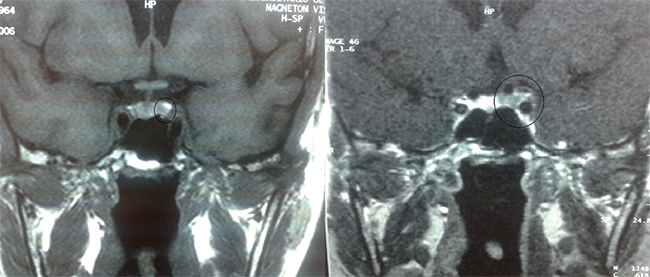

Mujer de 41 años con IMC 24 kg/m2, que en un estudio por glucemia basal alterada e hipertensión arterial se detectó cifras compatibles con hipercortisolismo. En el interrogatorio dirigido refería alteraciones menstruales, hirsutismo, aumento de tejido adiposo a nivel abdominal y debilidad proximal en miembros inferiores. Presentaba cortisol libre urinario (CLU) 387 µg/24 h (4,30-176,00 µg/24 h); Cortisol tras 1 mg de dexametasona 16 mcg/dL; Cortisol nocturno 16,7 mcg/dL (< 1,8 mcg/dl) (Cortisol 8 h: 20,9 mcg/dl). Para el diagnóstico etiológico realizamos ACTH 158 pg/ml; Cortisol tras 8 mg de dexametasona 4,4 mcg/dl; Estimulación con Vasopresina con la que se constató una elevación de la ACTH de 150% y cortisol 50%. Todo ello orientaba a un origen hipofisario por lo que se realizó una resonancia magnética de hipófisis que mostraba una lesión hipointensa cercana al seno cavernoso izquierdo de 5 mm que podría corresponder a un adenoma hipofisario con mínima lateralización contralateral del tallo (Figura 1).